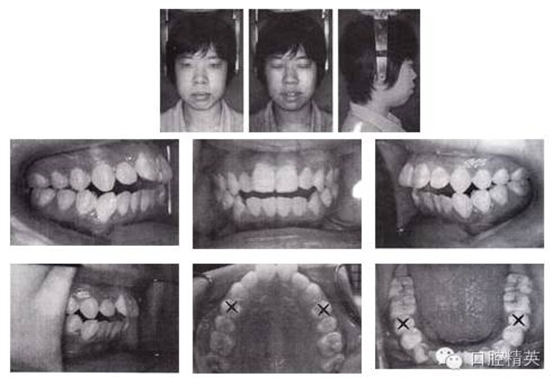

姓名:蘇某 年齡:18歲 性別:女

主訴:口唇前突、開(kāi)頜,求矯治。

檢查:恒牙列,雙側(cè)磨牙中性偏遠(yuǎn)中關(guān)系,11、12 、13 、21、22 、23中度開(kāi)頜,上下頜牙列輕度擁擠。正面觀,面型左右對(duì)稱;側(cè)面觀,雙頜前突,明顯開(kāi)唇露齒,下頜頦部發(fā)育不良致后縮。顳下頜關(guān)節(jié)無(wú)異常。

圖3-1 矯治前面像及口內(nèi)像(開(kāi)始矯治 2002-08-25)